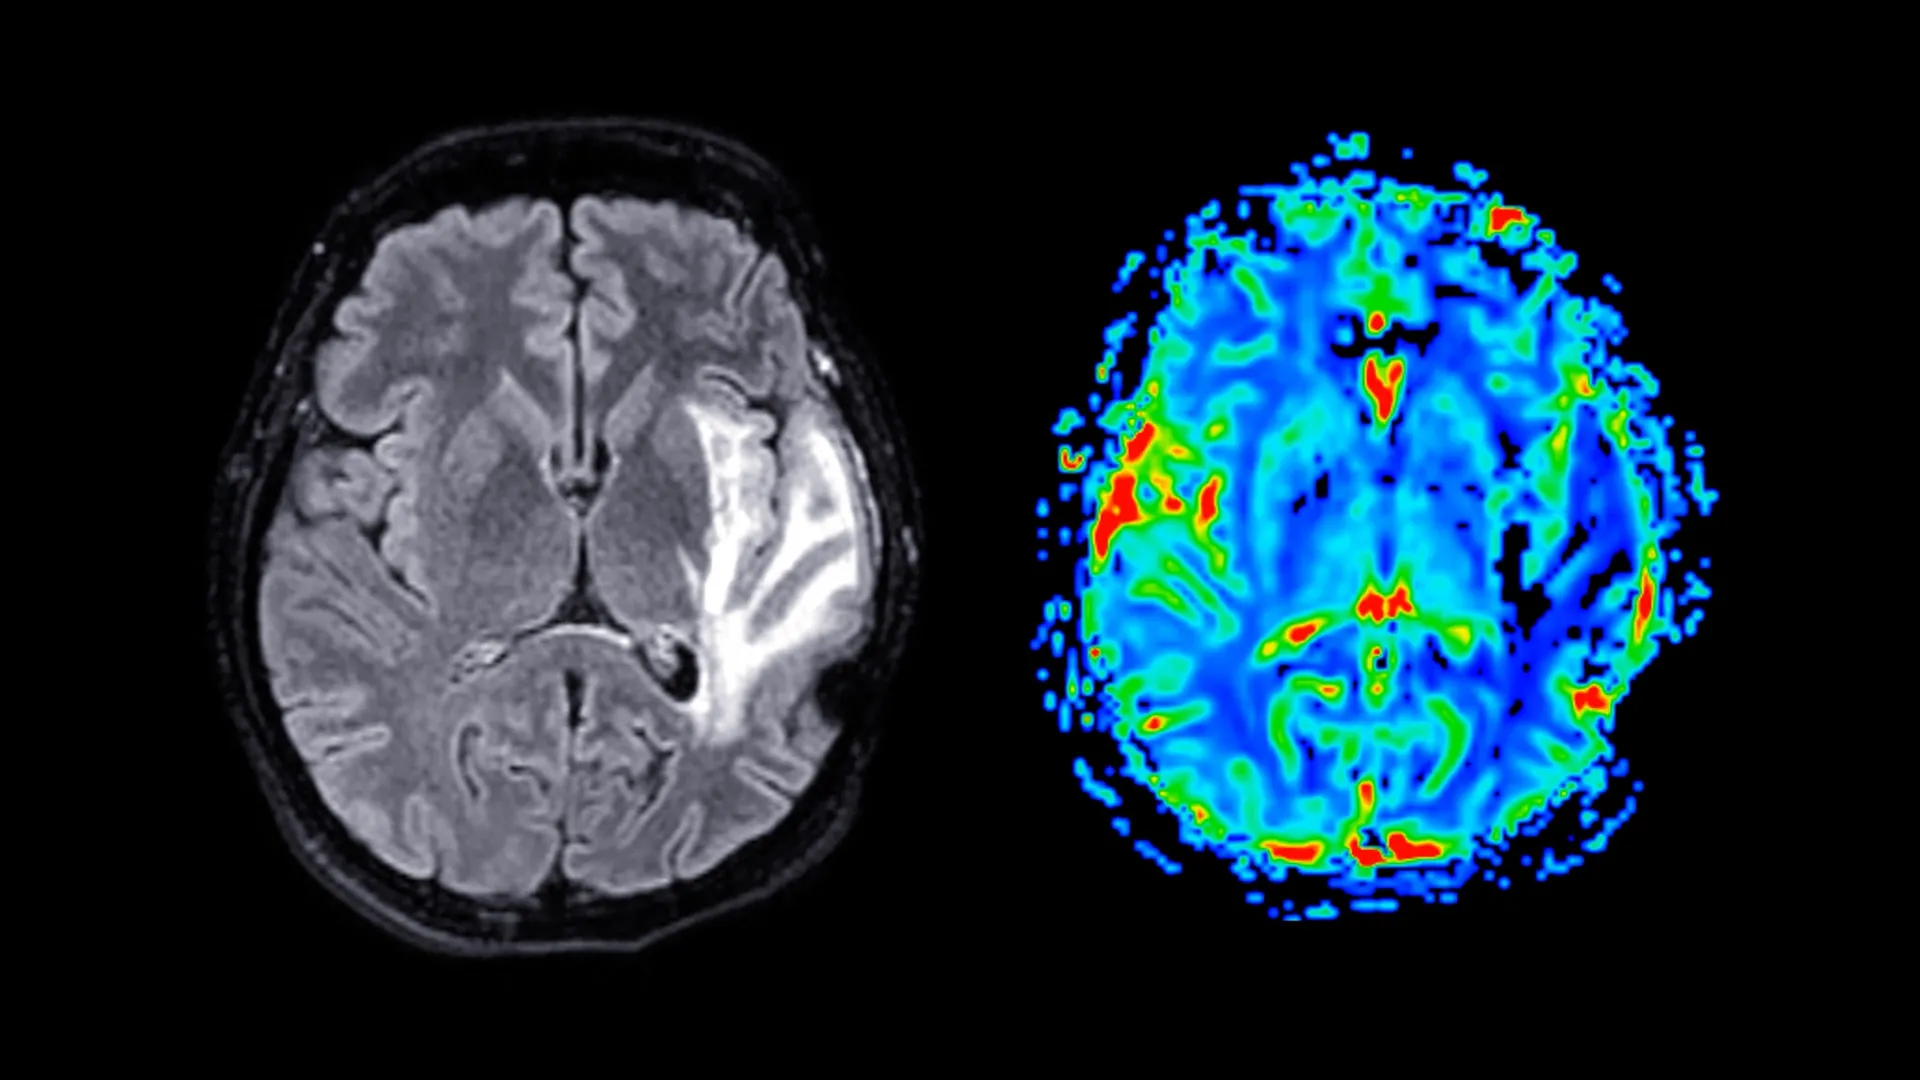

Participants were invited to complete a series of detailed questionnaires designed to capture information pertaining to menopausal symptoms, their psychological well-being, established sleep patterns, and their general health status. A subset of these participants also engaged in a battery of cognitive assessments, meticulously designed to evaluate their memory retention capabilities and their speed of response. Furthermore, approximately 11,000 women underwent advanced magnetic resonance imaging (MRI) scans, a non-invasive neuroimaging technique that provided researchers with high-resolution insights into the structural characteristics of their brains, enabling the detection of subtle variations in volume and organization. The average age at which participants reached menopause was approximately 49.5 years, with those prescribed HRT typically initiating treatment around the age of 49, underscoring the proximity of HRT initiation to the menopausal transition itself.

The neuroimaging component of the study yielded significant insights into structural brain changes. Magnetic resonance imaging revealed that post-menopausal women exhibited substantial reductions in grey matter volume, a finding that held true regardless of their HRT usage. Grey matter, the densely packed region of the brain composed primarily of neuronal cell bodies, is fundamental to a wide array of cognitive functions, including information processing, motor control, memory consolidation, and the intricate regulation of emotions. The most pronounced reductions in grey matter were observed in key brain regions: the hippocampus, a structure critically involved in the formation and storage of new memories; the entorhinal cortex, which serves as a vital conduit for information transfer between the hippocampus and other brain areas; and the anterior cingulate cortex, a region implicated in executive functions such as emotional management, decision-making, and focused attention.

The identification of these affected brain regions carries potentially significant implications for understanding women’s long-term neurological health. Professor Barbara Sahakian, the senior author of the study from the Department of Psychiatry, highlighted that the brain areas exhibiting these structural differences are precisely those that are typically impacted by Alzheimer’s disease. This observation leads to the hypothesis that menopause could render women more susceptible to neurodegenerative conditions later in life. While acknowledging that this is not the sole determinant, Professor Sahakian proposed that these menopausal-induced brain changes might contribute to the observed epidemiological phenomenon of nearly twice as many dementia cases occurring in women compared to men, suggesting a potential link between the menopausal transition and increased vulnerability to cognitive decline and dementia.